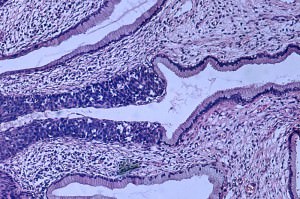

Первичный диагноз ставится при гинекологическом осмотре. Для подтверждения или уточнения диагноза проводится цитологическое обследование, с последующим гистологическим исследованием в случае сомнительного диагноза. В зависимости от возраста женщины, распространенности рака, степени его развития и многих других факторов выбирается тактика лечения. Это может быть операция: от ограниченной по объему оперируемых тканей конизации до тотальной резекции матки и ее придатков. Используется также химио– и лучевая терапия, сочетание методов.